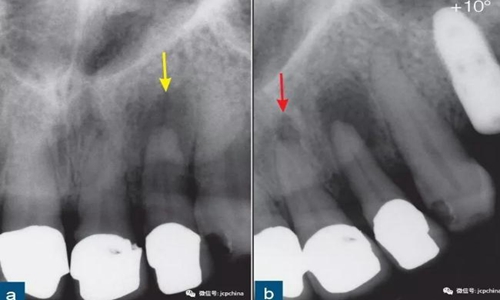

第一張根尖片22牙(黃色箭頭)的根尖周透射影清晰可見。第二張根尖片(水平遠(yuǎn)中方向偏移10°)顯示21牙的根尖周“透射影”(紅色箭頭)。此“透射影”實(shí)際上是切牙孔,該解剖噪點(diǎn)和根尖周透射影的表現(xiàn)類似。

所以,經(jīng)驗(yàn)不足的臨床醫(yī)生很容易誤診。